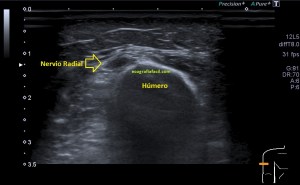

237. Neuropatía del Nervio Radial.

En el Post de hoy te cuento el caso de un paciente que llega a la sala de ecografía con una petición de su médico generalista para el estudio de un hombro por impotencia funcional, he de decir que es la primera vez que no pude realizar el estudio completo del protocolo de hombro por el dolor tan intenso que padecía el paciente.

Indagando un poco es su historial en búsqueda de alguna prueba de imagen que me diese un poco de luz y tras consultar con el radiólogo encontramos que al paciente se le realizó una ecografía para posible drenaje por un sangrado en el brazo y ante una sospecha de síndrome compartimental que finalmente fue descartada por los especialistas en ese lugar comentado previamente.

La ecografía reveló estos hallazgos:

Durante la exploración del hombro me encontré un hallazgo que bien por la experiencia o por la intuición, quizá ambas, busco en cada protocolo de hombro que hago y que es punto de dolor irradiado habitual del hombro justo donde el radial pasa por la parte posterior del húmero antes de buscar la cara antero lateral externa del codo, encontrándome estas imágenes que te comento semiológicamente y que son típicas de neuropatía.

6

En el lugar comentado anteriormente, encuentro una estructura hipoecogénica que no es compatible con la normalidad de un nervio, como si lo es la imagen 6A que te enseño a continuación donde el nervio radial contralateral te dice cómo es un nervio radial normal en el mismo punto que el de la imagen 6, mira:

7

El corte longitudinal del nervio afectado es muy llamativo, tanto en su aspecto ecográfico como en su tamaño y puedes verlo en las imágenes 7 y 8.

Finalmentes la imágenes 10 y 11 donde vas a ver una comparativa en eje corto y eje largo donde vas a ver el lado derecho del paciente patológico y el lado contralateral, normal. Observa y compara, el aspecto y el tamaño y vas a ver como es más que evidente un cambio en la ecogenicidad de la ecoestructura del nervio llegando a ser el doble de grande y mucho más hipoecogénico.